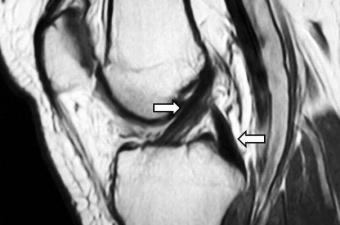

ACL Reconstruction

Screen Shot 2015-06-21 at 11.15.39 pm torn acl Bookmark the permalink.